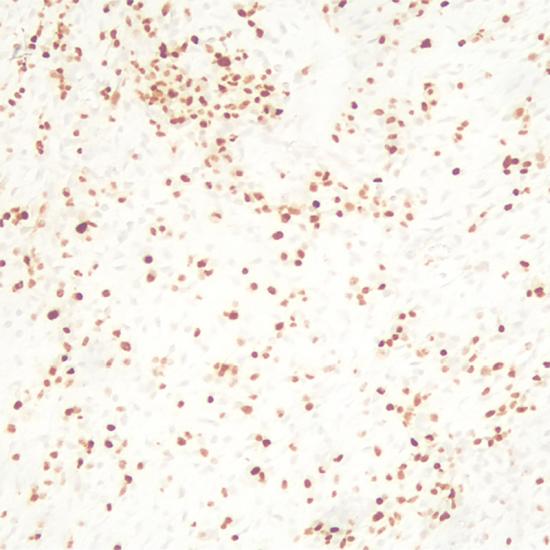

NKX2.2

NKX2.2抗體試劑(免疫組織化學(xué)法) 閩廈械備20190289號

• 預(yù)處理:

熱修復(fù)

• 陽性部位:

細(xì)胞核

• 陽性對照:

胰腺組織

• 適用組織:

石蠟

• 免疫顯色試劑:

iVision?

• 產(chǎn)品編號:

AM0843

• 種屬來源:

鼠單抗

• 克隆號:

TLM0843

• 手工規(guī)格/ML:

1、3、6、0.2(濃縮液)

• 儀器規(guī)格/人份:

30、60、120

NKX2.2是轉(zhuǎn)錄因子NKX家族中的一員,對中樞神經(jīng)系統(tǒng)和胰腺神經(jīng)內(nèi)分泌分化非常重要,表達(dá)于人的腦、胰腺、垂體和胃腸道等正常組織。NKX2.2對尤文氏肉瘤具有高敏感性和特異性,有助于尤文氏肉瘤的診斷和鑒別診斷。